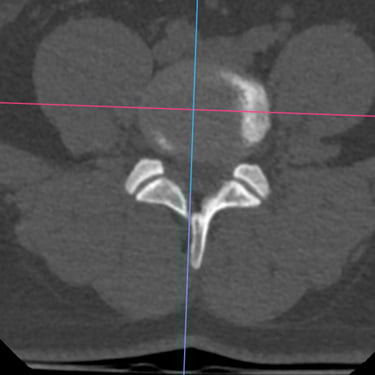

El síndrome postdiscectomía se presenta cuando persiste o reaparece el dolor lumbar y radicular después de una cirugía previa de hernia discal. Puede estar asociado a inestabilidad segmentaria, fibrosis epidural o degeneración discal progresiva. Cuando el manejo conservador no logra aliviar los síntomas, la fusión intersomática transforaminal (TLIF) mínimamente invasiva constituye una alternativa eficaz. Este procedimiento permite descomprimir las estructuras nerviosas, restaurar la altura discal y estabilizar el segmento afectado con menor daño muscular. La técnica mínimamente invasiva favorece menor sangrado, recuperación más rápida y mejores resultados funcionales.